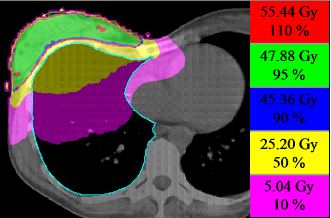

A clinical case was set-up to examine the efficiency of our proposed segmentation algorithms. For a patient with cancer of the right breast, electron irradiation plans using various segmentation settings and different optimization constraints were created with a self-designed IMRT optimization programme based on our previous studies [9]. The planning target volume was the right breast, which should receive a total dose of 50.4 Gy (1.8 Gy per fraction). In addition, the target volume should be covered by the isodose line ( of the prescribed dose). The ipsilateral lung was considered to be organ at risk.

The plan quality was evaluated by means of dose volume histograms that indicate the amount of dose delivered to a certain volume of the patient (here: the right breast and the right lung). Thus, dose homogeneity in the target volume and dose exposure to the organs at risk can be examined. In Figure 7, the dose volume histograms for both optimization settings demonstrate that almost identical dose distributions can be achieved using smaller or larger minimum MLC openings (cf. setting and ). In fact, the treatment plan could be slightly improved by use of a minimum vertical gap parameter of which avoids single leaf openings and closings.